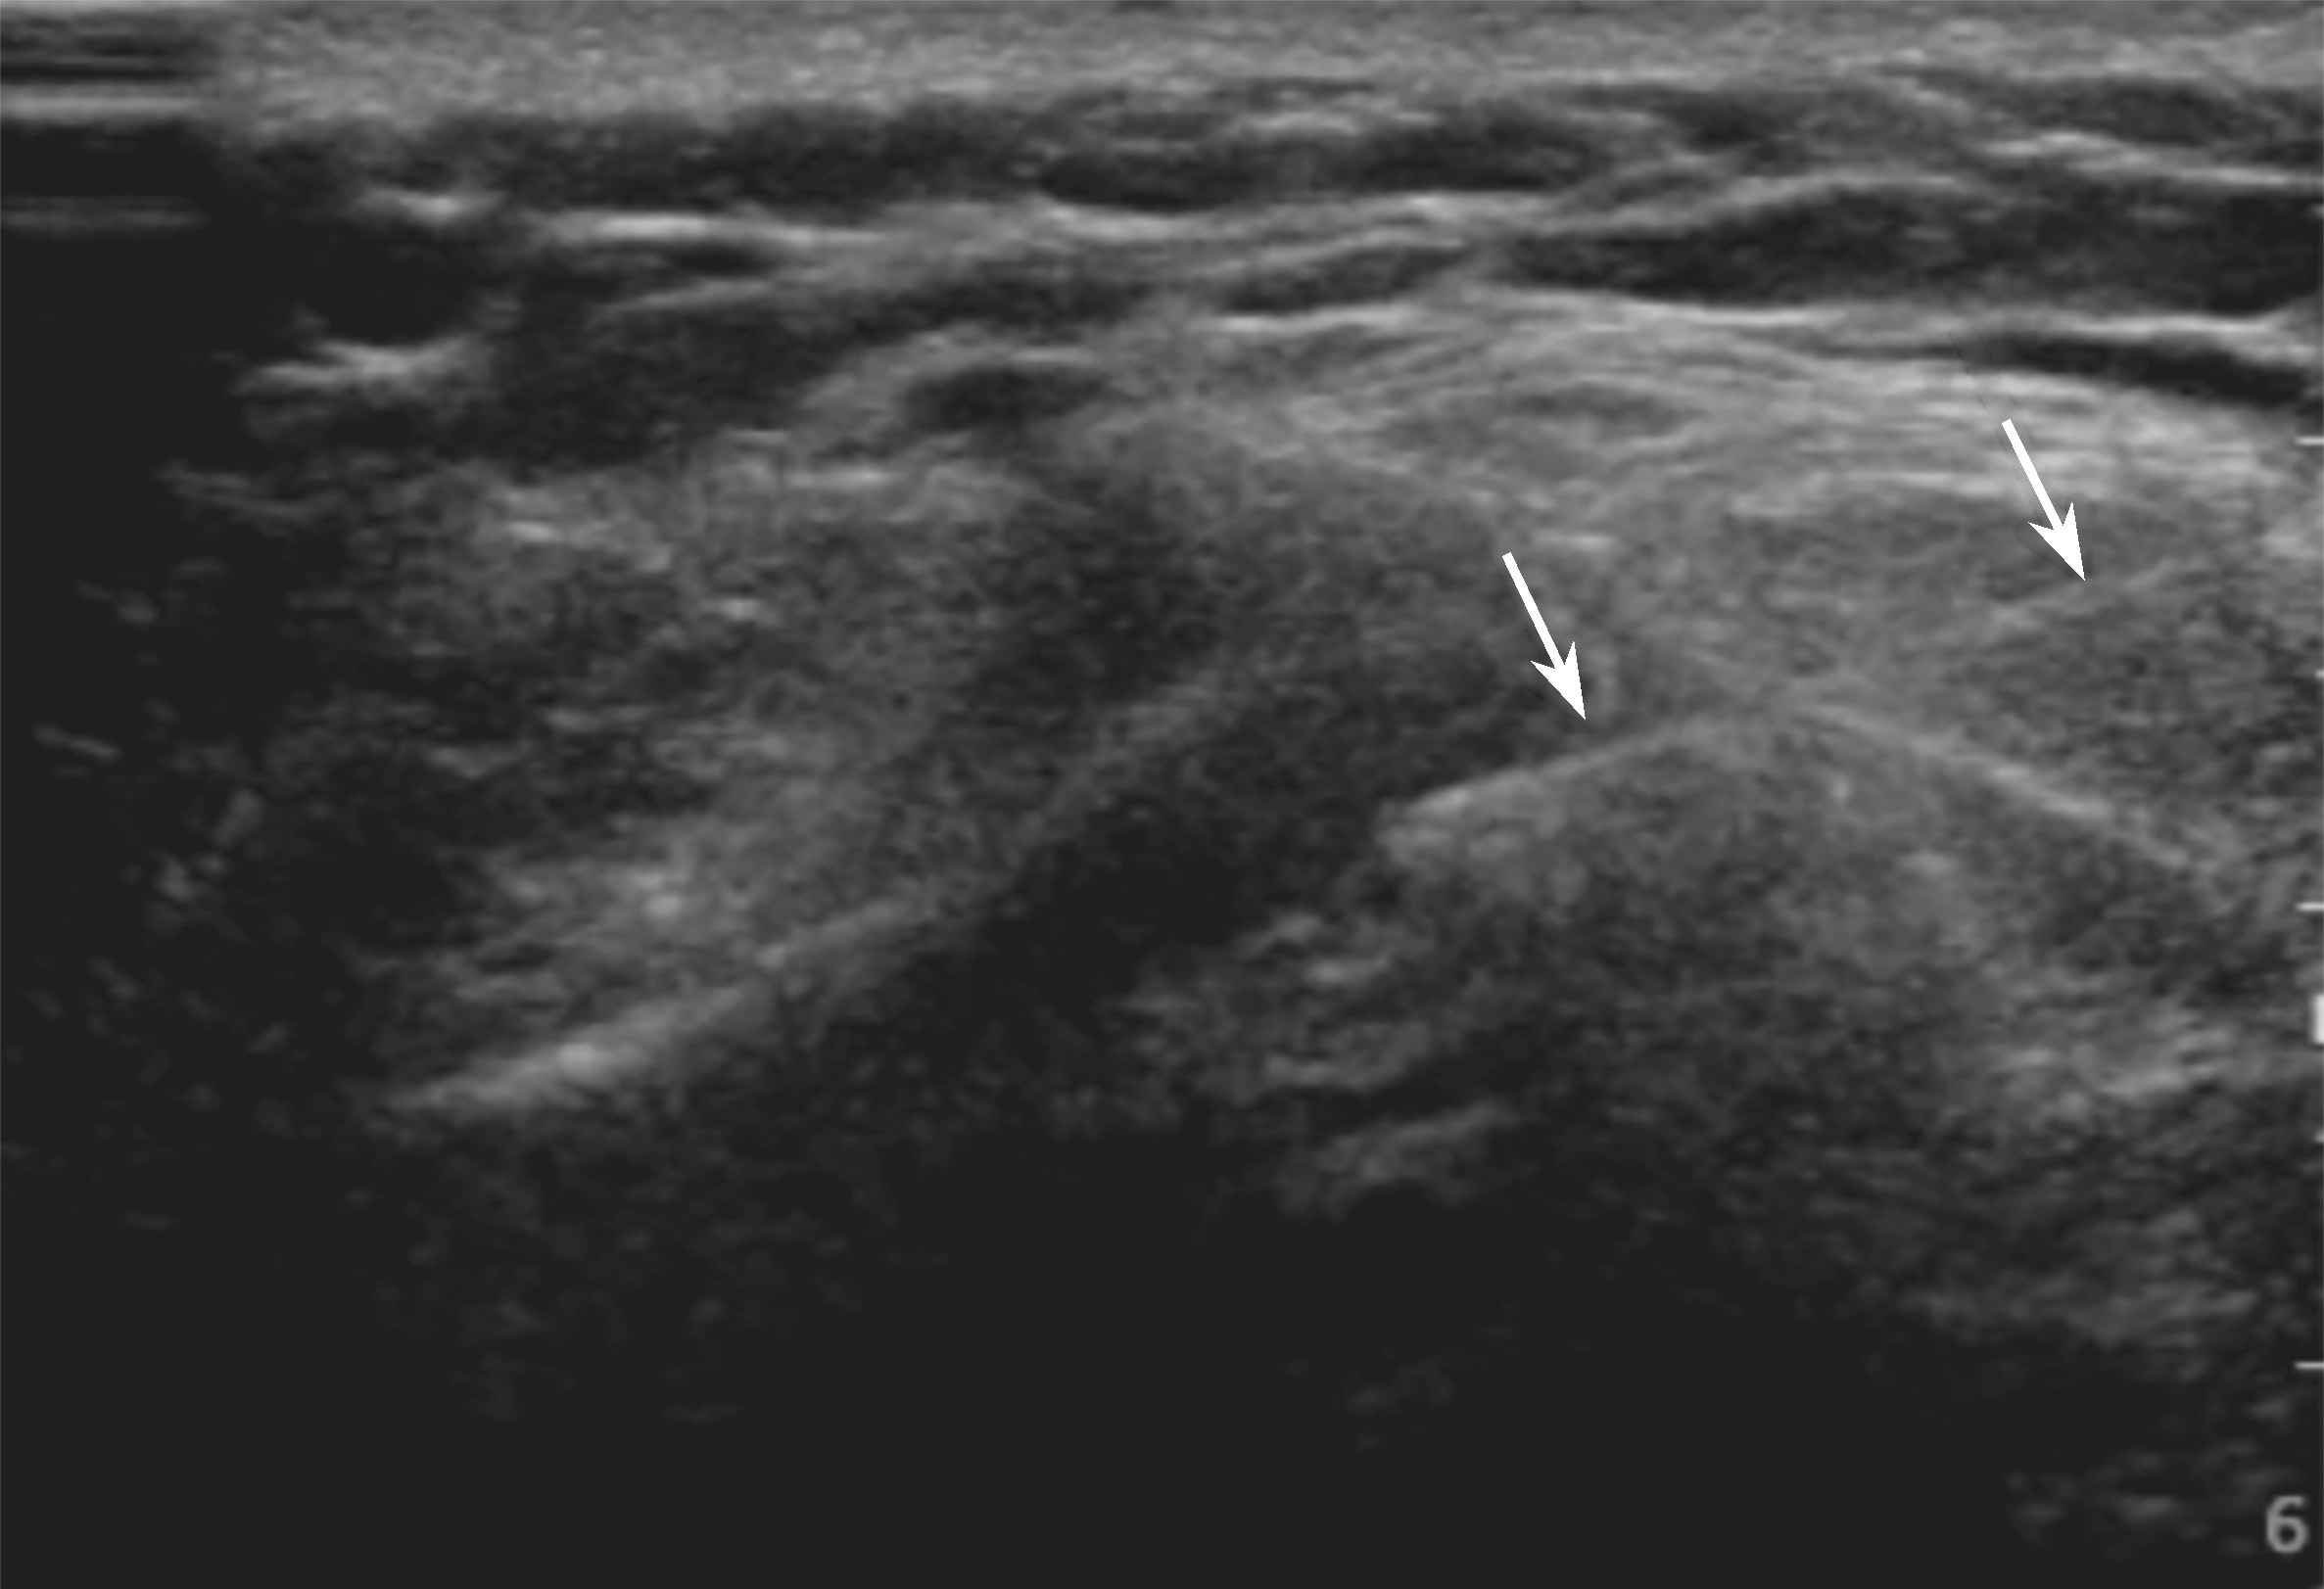

▲ 图2-4-4 超声引导下类风湿肩锁关节炎伴骨侵蚀介入治疗超声图

箭头:穿刺针